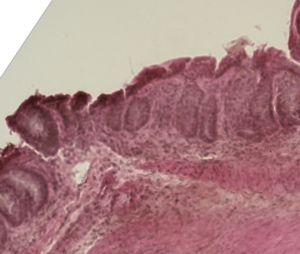

Mouse colon histology of acute graft versus host disease.png

قولون فأر مصاب بمرض الطعم ضد المضيف المزمن.